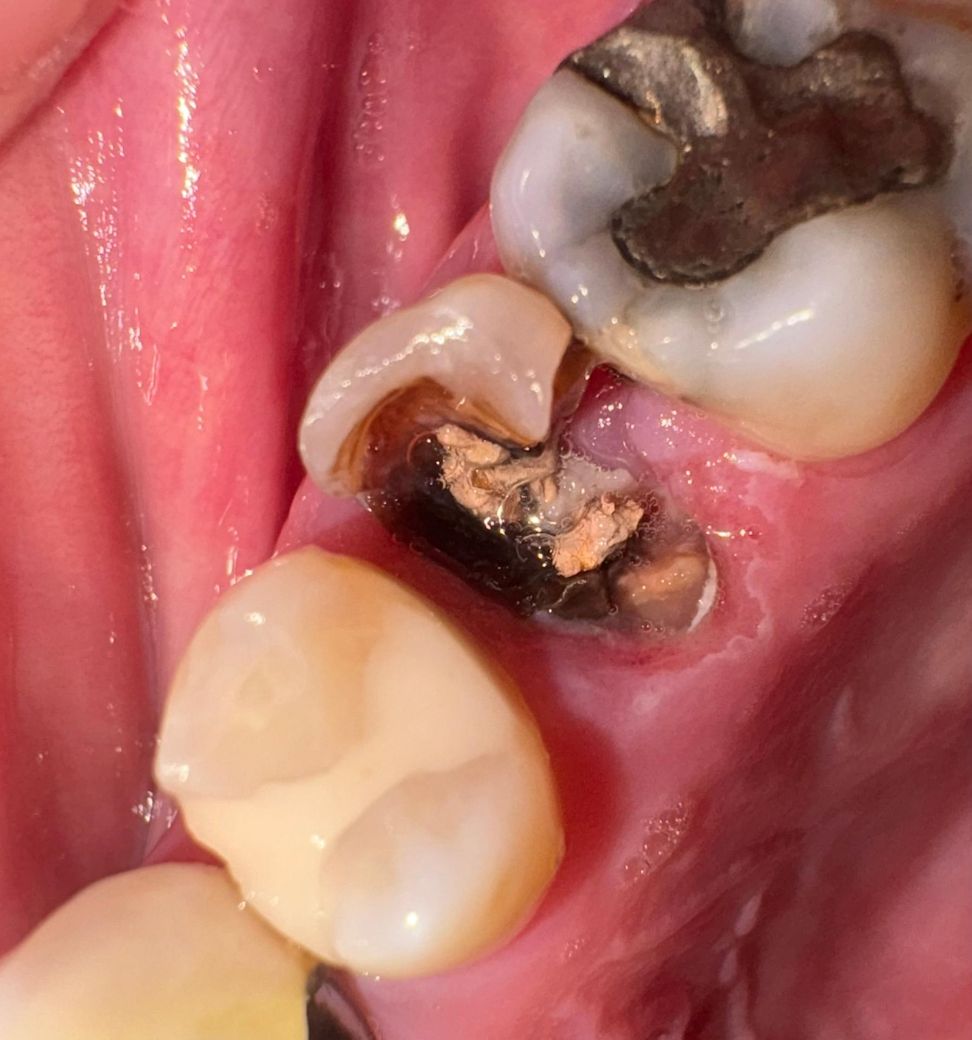

아래의 사진처럼 좌측 상단 어금니가 어제 저녁 식사 중에 부러졌습니다. 과거 신경치료를 진행 했었던 치아인거 같구요.. 통증은 평상시 뿐만 아니라 식사시에도 전혀 없습니다.

• 1번 째 사진